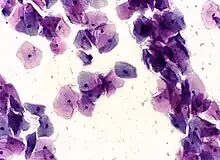

Pap tests commonly examine epithelial abnormalities, such as metaplasia, dysplasia, or borderline changes, all of which may be indicative of CIN. Nuclei will stain dark blue, squamous cells will stain green and keratinised cells will stain pink/ orange. Koilocytes may be observed where there is some dyskaryosis (of epithelium). The nucleus in koilocytes is typically irregular, indicating possible cause for concern; requiring further confirmatory screens and tests.